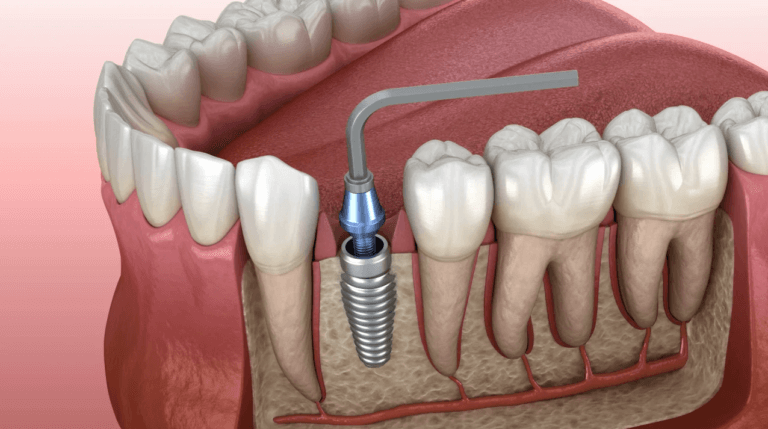

Dental Implants | Permanent Tooth Replacement

Get durable, natural-looking dental implants at Khan Dental Care. Replace missing teeth and enjoy a confident smile with real-tooth comfort and strength.

Types of Dental Implants – Conventional vs Immediate Implants

Learn how conventional two-stage dental implants provide stable, durable, and reliable tooth replacement with a 3-month healing period.

Conventional Dental Implants –Two-Stage Surgery & Long-Term Success

Discover conventional dental implants with a two-stage surgery process. Ideal for patients with good bone support, these implants offer high stability and long-term success, with crowns placed after a minimum 3-month healing period.

Immediate implants provide quick, flapless tooth replacement, suitable for diabetic and medically compromised patients, with restoration within one week.

Immediate Dental Implants – Fast, Minimally Invasive Tooth Replacement

Explore immediate dental implants for fast, minimally invasive tooth replacement. Loaded within one week, they are ideal for diabetic patients, those with medical issues, or anyone seeking quicker healing and aesthetic restoration.